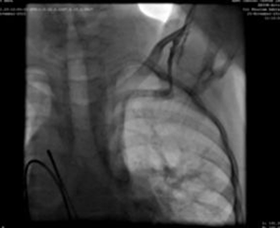

We used a 9F delivery sheath, which was advanced over and placed in the descending aorta over the super-stiff guidewire. A МемопartТМ cone shape PDA occluder 14/12 mm, was attached to the delivery cable and progressed across the delivery sheath. The placement of the occlude was proper with no residual flow.

Хирургический успех, отсутствие серьезных интраоперационных усложнений, эхокардиография через 24 часа после окклюзии показывает хорошее размещение, отсутствие остаточного шунта на дефекте.